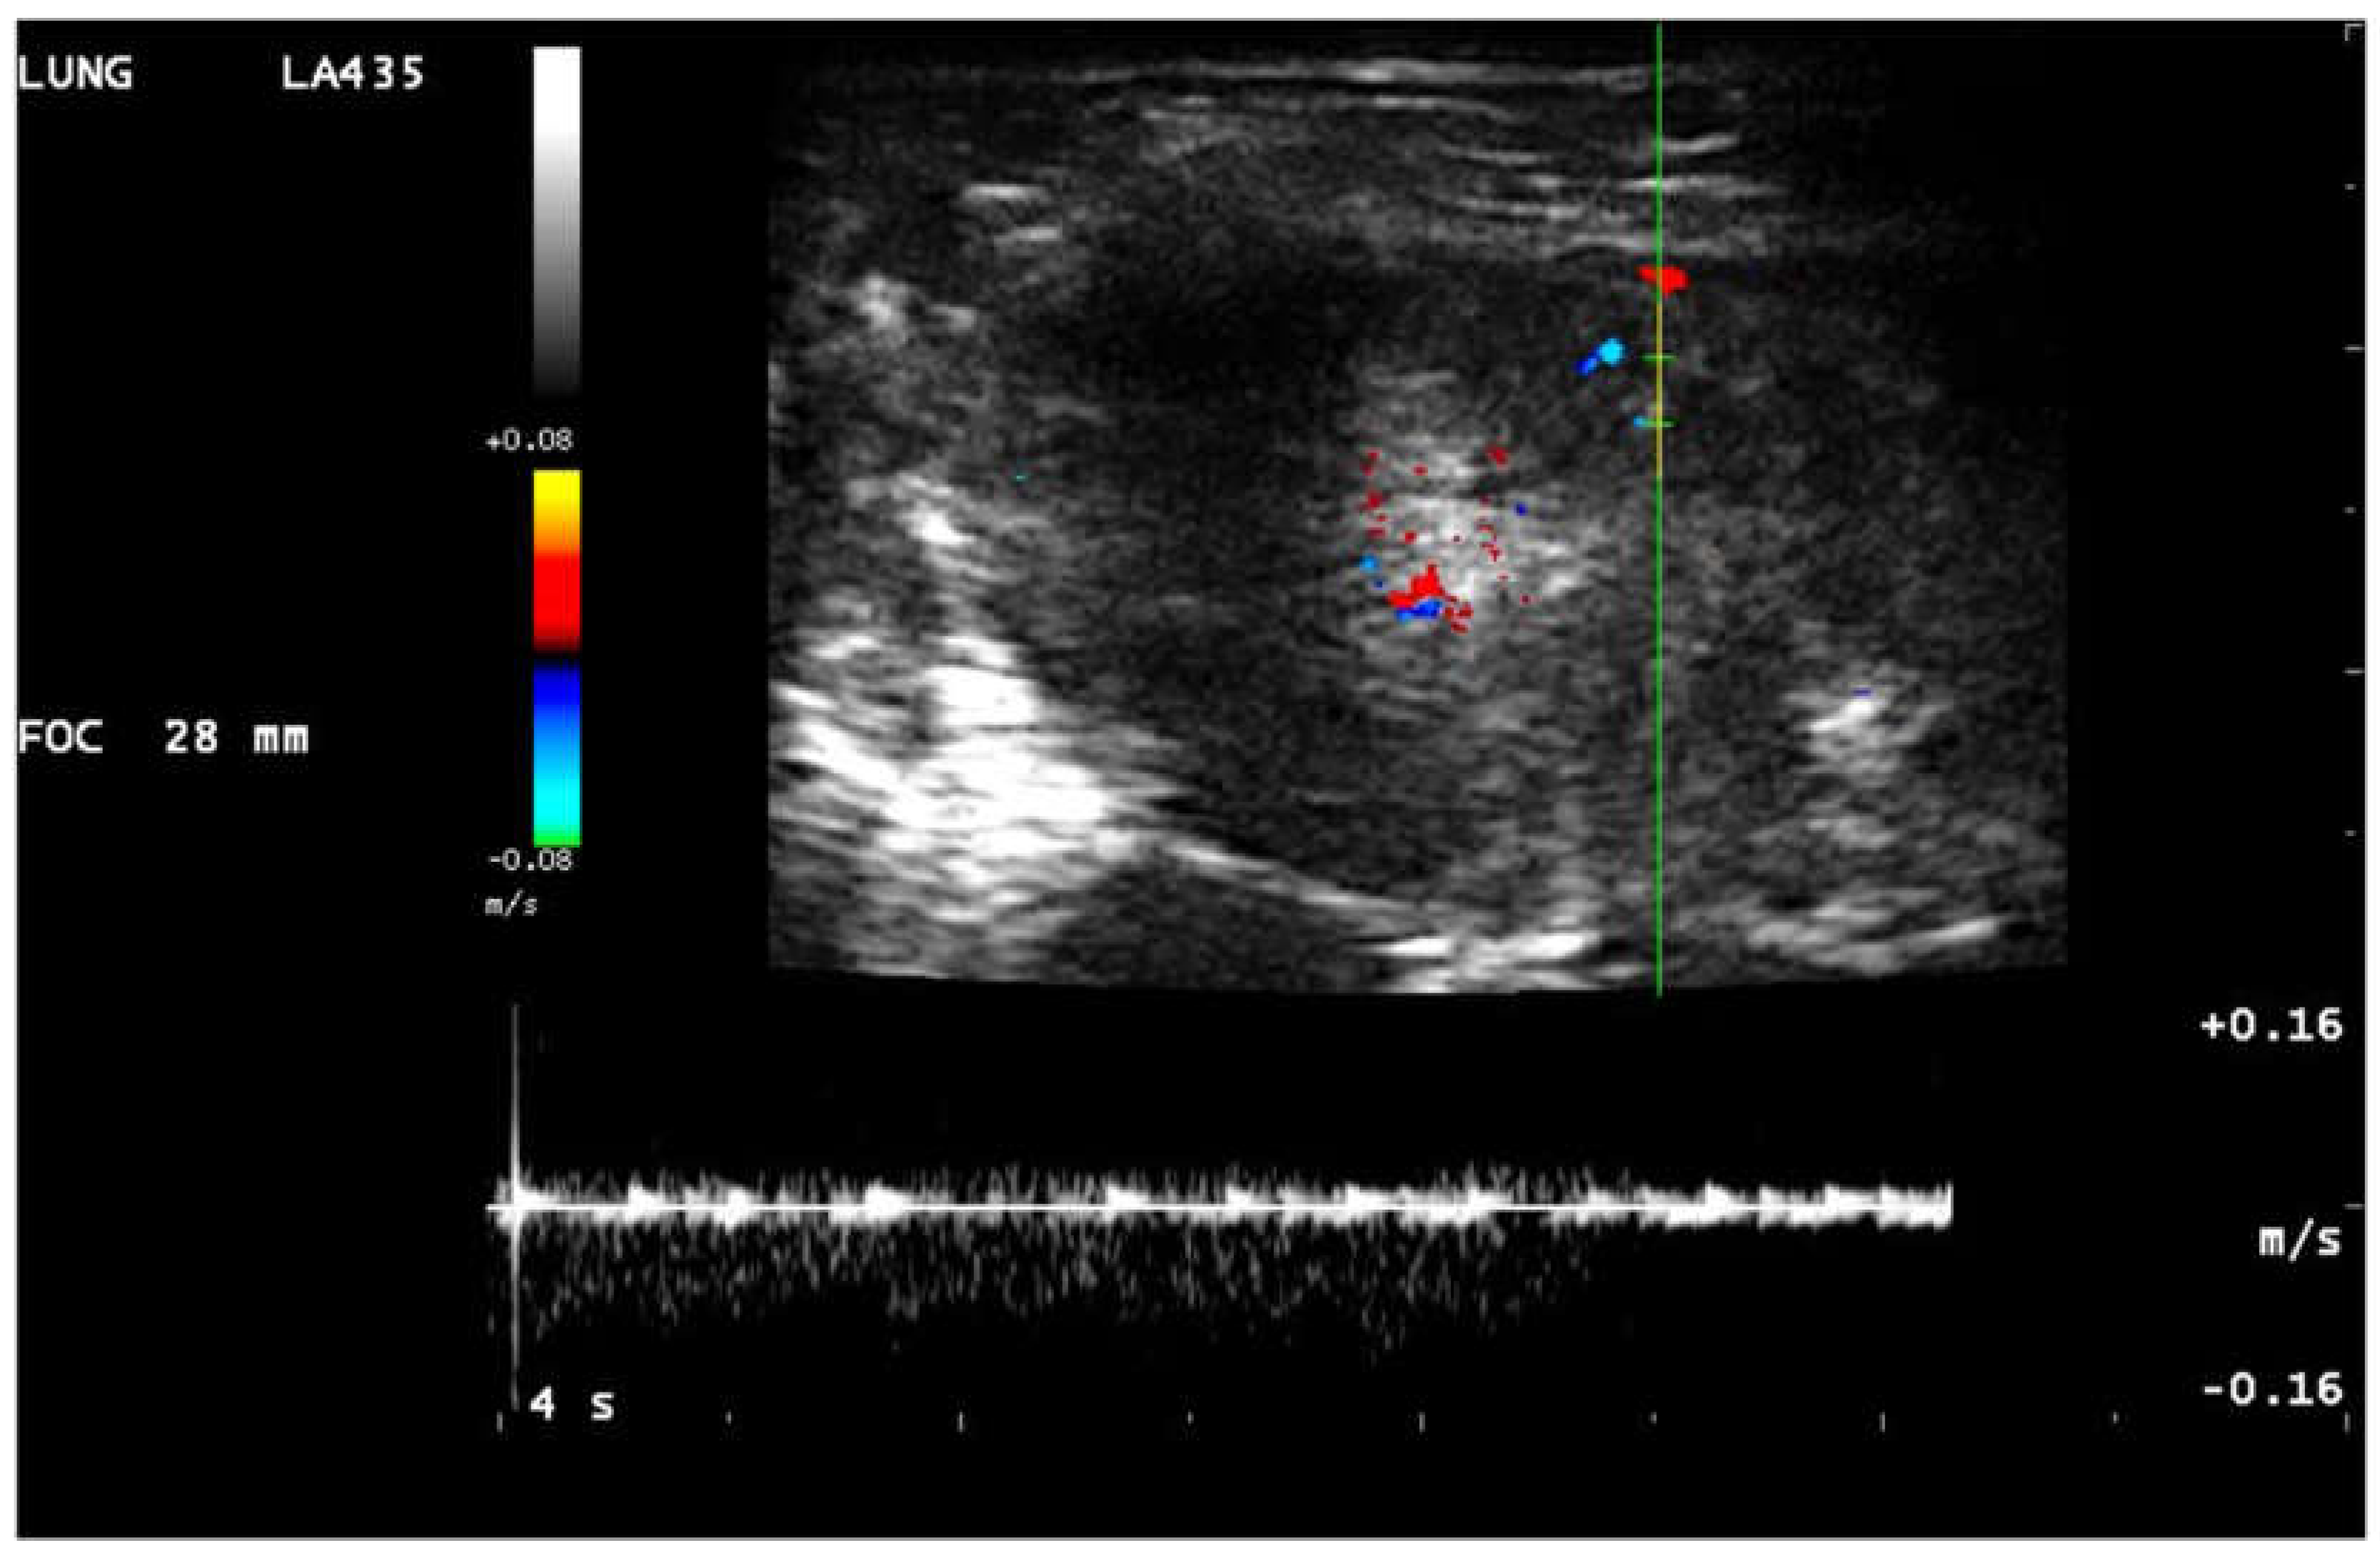

| CD | color doppler | |

| Hv | chaotic type vascularity | |

| Pv | penetrating type vascularity | |

| Rv | residual type vascularity | |

| Tv | tree-like vascularity | |